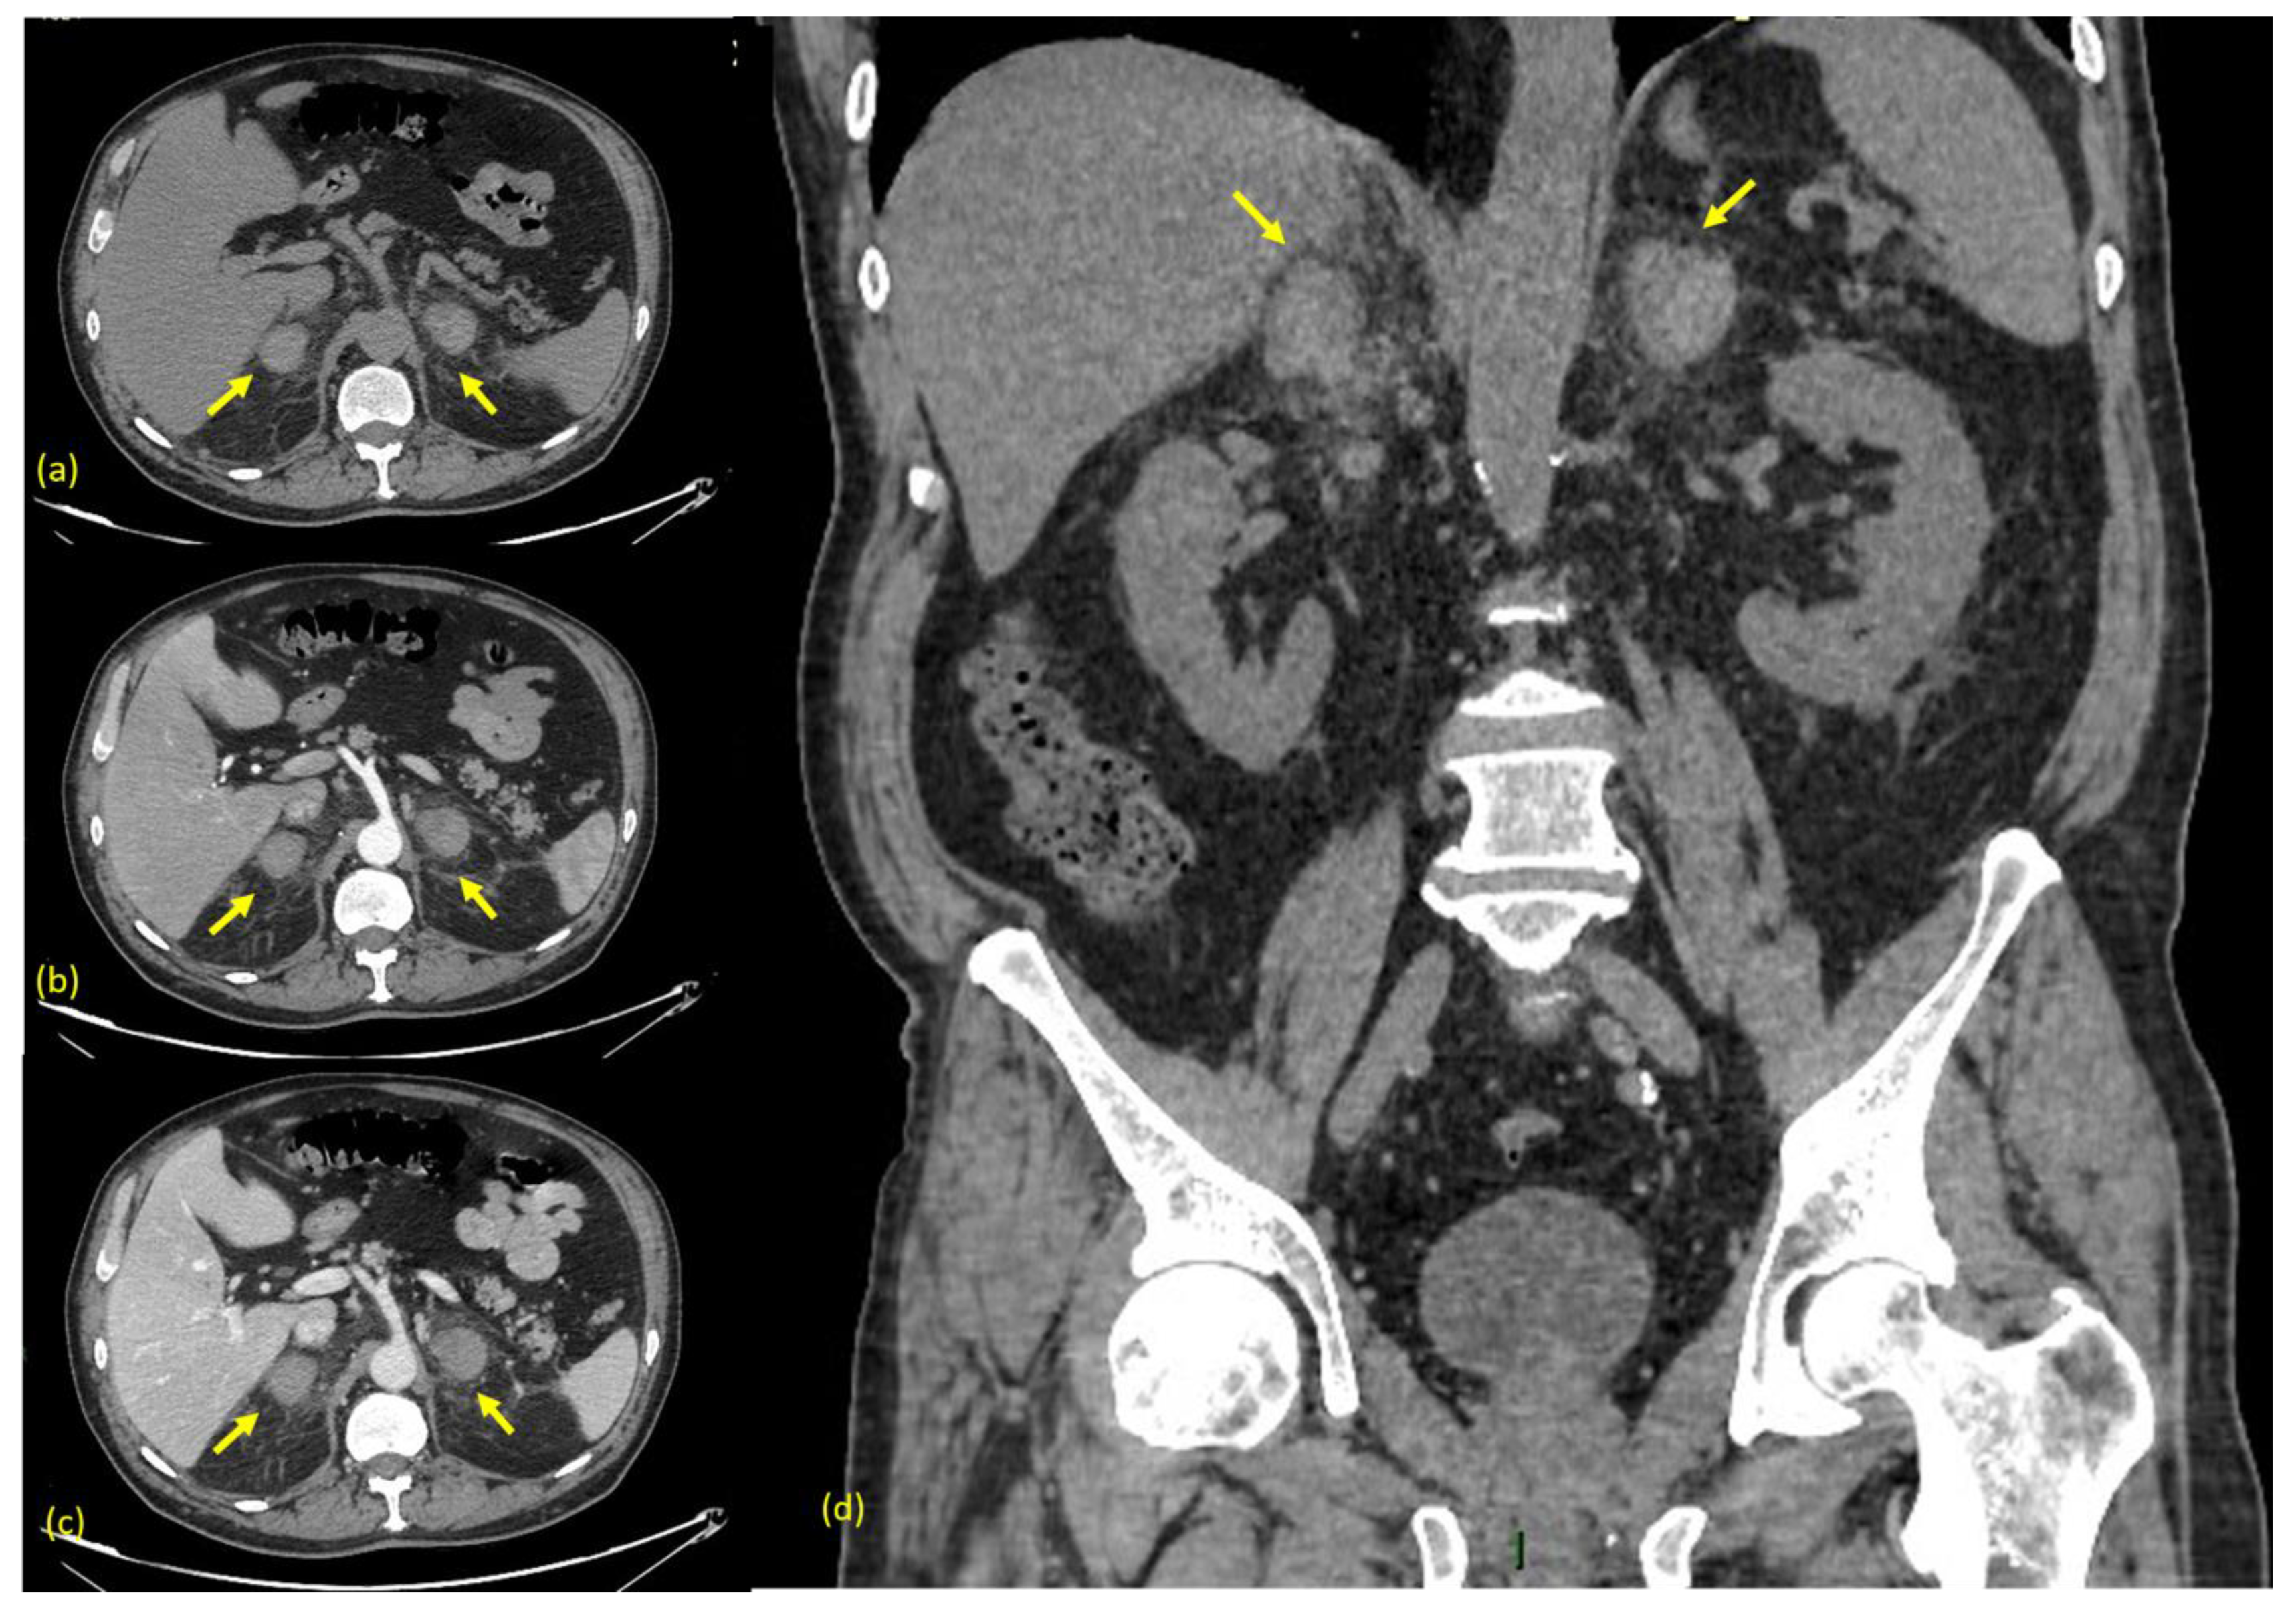

An urgent ultrasonography scan (US) was performed with a convex transducer that revealed an enlargement of both adrenal glands with inhomogeneous echogenicity (Figure 1).

Figure 1. (a) Arrow indicates the right adrenal gland. (b) Arrow indicates the left adrenal gland. The US Scan shows an enlargement of both adrenal glands with inhomogeneous echogenicity. The right gland measures 41 × 26 mm while the left adrenal gland measures 43 × 30 mm.

In the management of a patient presenting abdominal pain, ultrasonography (US) is usually the first modality to be performed. The pattern of echogenicity of an adrenal hematoma depends on the time since the onset.

During the first days, a hematoma has the look of a mass with inhomogeneous echogenicity. As days go by, the hematoma tends to liquefy, starting to show peripheral heterogeneous echogenicity with a hypoechoic core. Eventually, it tends to become anechoic and appears similar to a pseudocyst. Color Doppler US can be helpful for confirming the absence of vascular signals [20].